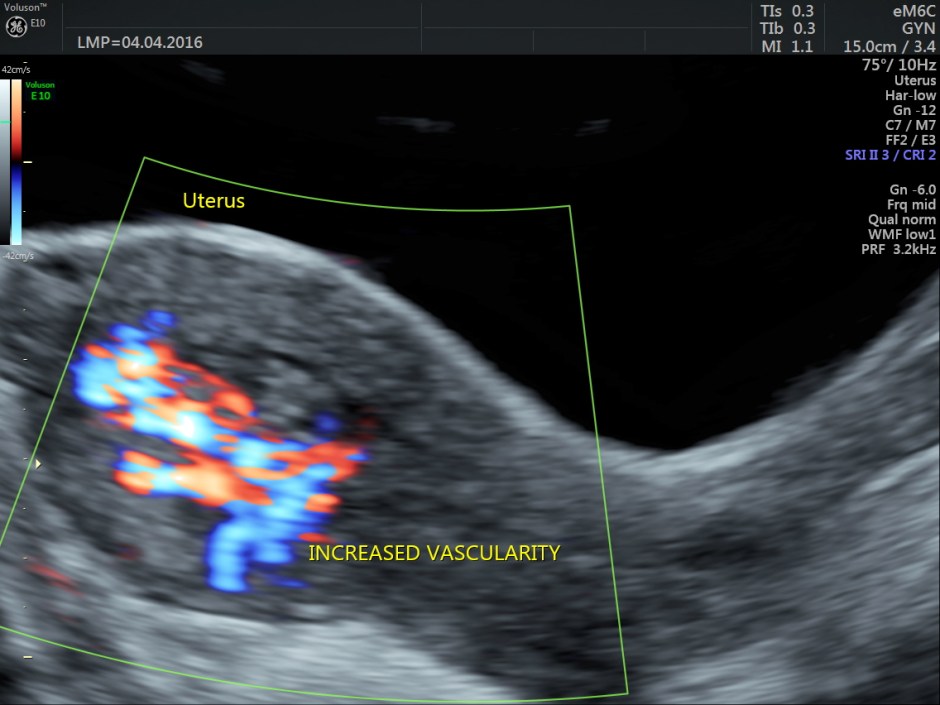

Colour and Power Doppler images are given below.

Trans abdominal :

Increased vascularity is seen in the posterior aspect